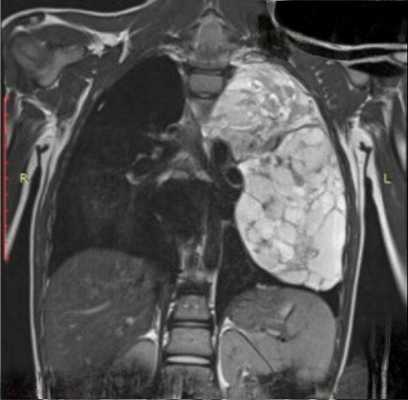

Диагноз выставляется с учетом анамнеза, клинических проявлений, результатов инструментальных и лабораторных исследований. Пациентов с подозрением на метастазы в легких направляют на рентгенографию грудной клетки, позволяющую оценивать состояние легочной ткани, определять тип, характер и количество вторичных новообразований, наличие выпота в плевральной полости. Пациентам также назначают КТ легких - эта современная методика дает возможность выявлять мелкие метастазы диаметром менее 0,5 мм, в том числе расположенные субплеврально.

КТ ОГК. Множественные мягкотканные очаги в обоих легких у пациента с первичным раком предстательной железы

При необходимости снизить лучевую нагрузку (при метастазах в легких у детей, при многочисленных исследованиях для выявления первичного очага и метастатических поражений других органов, при продолжительном наблюдении) и подозрении на наличие мелких метастазов проводят МРТ легких - эта методика позволяет обнаруживать вторичные очаги диаметром менее 0,3 мм. Метастазы в легкие подтверждают на основании результатов цитологического исследования мокроты и плеврального выпота или гистологического исследования биоптата, полученного в процессе бронхоскопии, чрескожной пункционной биопсии легкого или (реже) открытой биопсии.